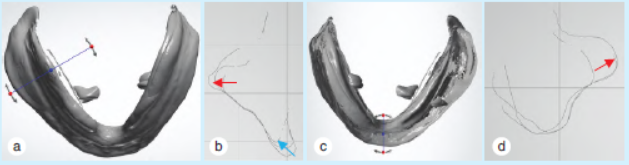

2.1义齿空间变化

拟合治疗前后扫描的义齿组织面形态,其差异反映了治疗前后的义齿空间变化量。义齿空间变化随治疗性义齿的戴用表现出的规律为下颌颊棚区的扩展,下颌舌骨区的适应性变化以及唇侧基托的扩展(图2)。

图2 义齿形态扫描所示治疗前后下颌义齿空间变化